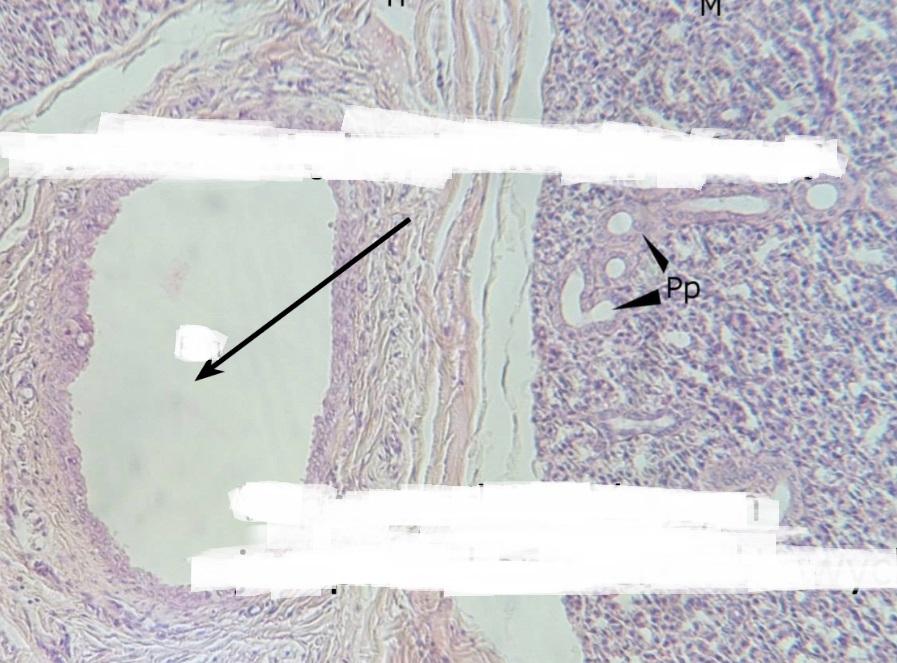

Pytanie 363

ślimak - te kilka jam (preparat rozwojowy z głowy szczura, okolice ucha wewnętrznego)